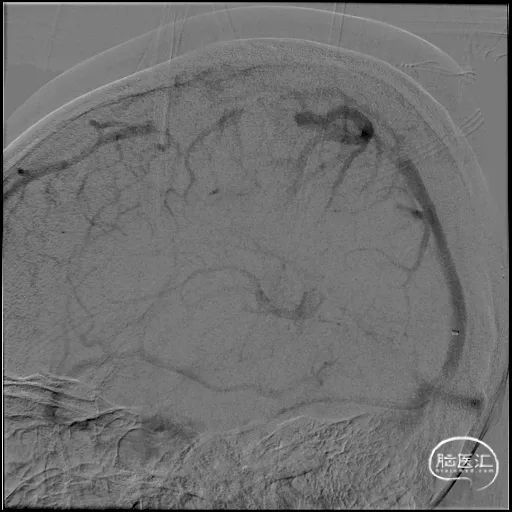

a) 经桡动脉造影明确病变情况:术中行右侧桡动脉及右侧股静脉双穿刺,动脉入路完成评估,静脉入路作为治疗通道,经桡动脉造影评估静脉期上矢状窦及横窦情况,明确上矢状窦、右侧横窦血栓形成。同时经颈静脉置入Neuron Max导引导管,逆行而上接近颅底破裂孔区。

2A 桡动脉入路,5F Simmons造影管超选右侧颈内动脉行造影评估,股静脉置入8F穿刺鞘,Neuron Max(0.088inch)在125cm MPA配合泥鳅导丝引导下进入右侧颈静脉。

2B 脑动脉造影静脉期可见上矢状窦显影不清,明确静脉窦血栓诊断。